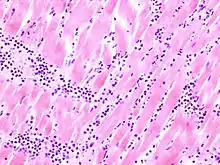

Acute myocardial infarction

Der Myokardinfarkt muss mind. 6 - 12 Stunden überlebt werden, bevor er morphologisch sichtbar wird!

Mikro: Koagulationsnekrose, Einblutungen. Die Myozyten zeigen eine verstärkte Eosinophilie und Kontraktionsbanden quer durch die Herzmuskelfasern. Typische Zellparameter wie Querstreifung, Zellkerne und Zellgrenzen gehen verloren. Das Infarktareal wird von einer Hyperämischen/hämorrhagischen Randzone begrenzt. Im Verlauf zunehmende leukozytäre Demarkation und Phagozytose des nekrotischen Gewebes, sowie Einwanderung von Fibroblasten mit Ausbildung eines narbigen Ersatzgewebes.

Makro: Lehmfarbene Abblassung mit hyperämischem/hämorrhagischem Randsaum.

![]() Akuter Myokardinfarkt, H&E. |

![]() Myokardinfarkt 7. Tag (Abräumphase), Sektionspräparat, H&E. |

![]() Akuter Myokardinfarkt, Kontraktionsbanden- nekrosen, PTAH. |